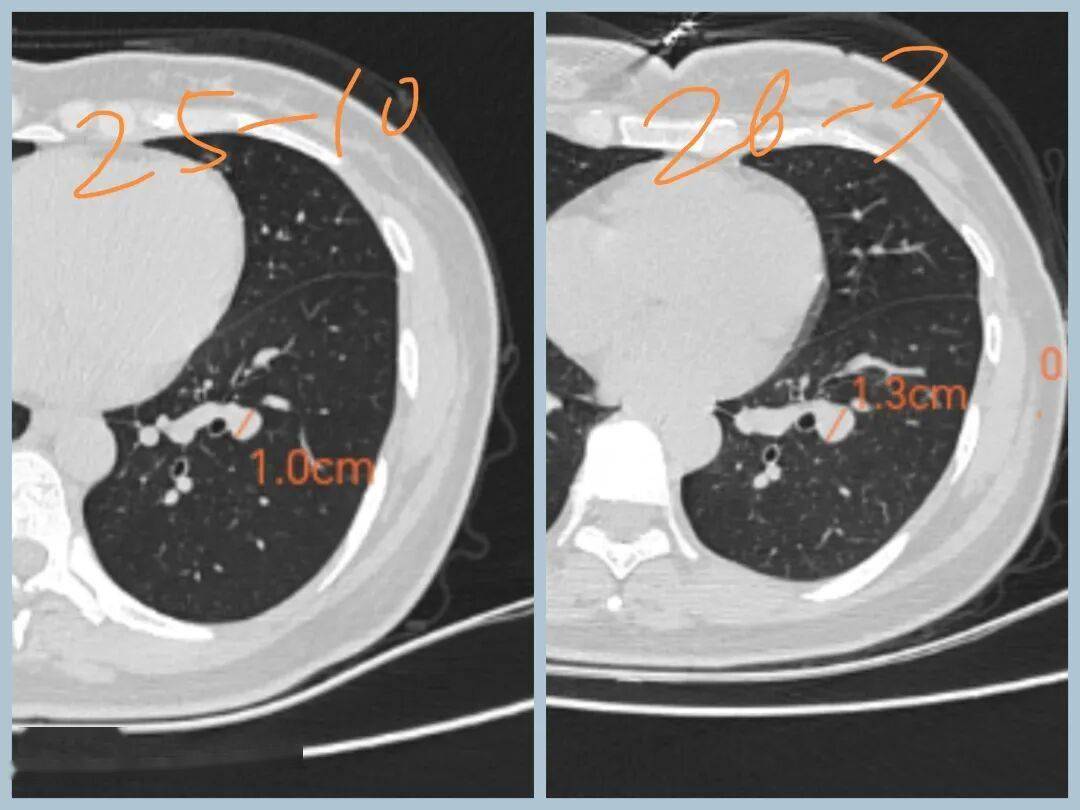

【病例3,网络咨询】

女性,30+,发现双肺结节5个月

分别是右肺上叶纯磨玻璃结节,大小约8mm

左肺下叶实性结节,大小约1cm

5个月后复查,右肺磨玻璃结节无变化,左肺实性结节增大

下一步怎么办:

1、磨玻璃结节无增大,原位癌可能,可继续观察

2、左下叶结节增大,有可能是低度恶性肿瘤,如类癌。也可能是良性病变,如错构瘤、硬化性肺泡细胞瘤。半年后再复查,继续增大,建议手术。

3、手术方式可 尝试剥除,若无法剥除,或为恶性,则行肺叶切除。